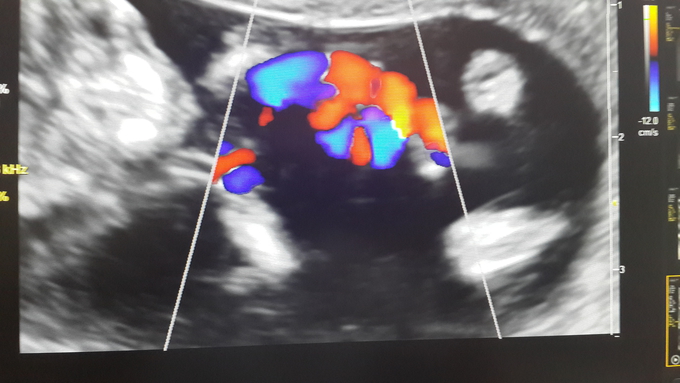

Медицинская визуализация: Признак Кюстнера-Чукалова